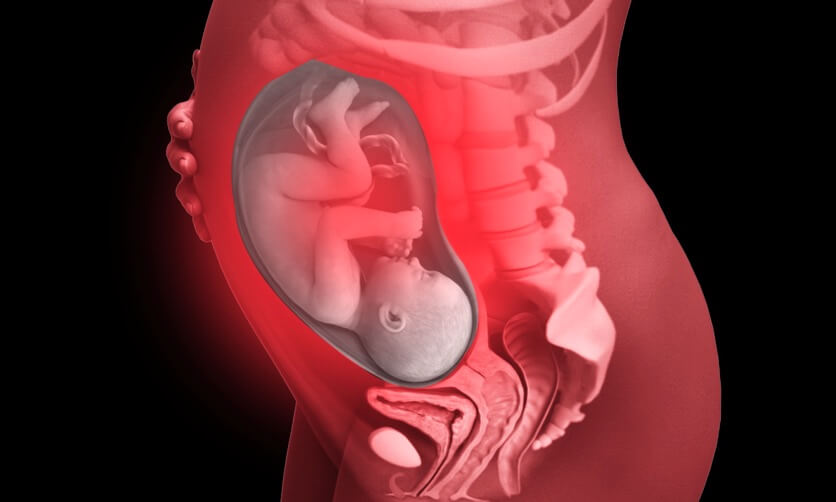

Our increasing understanding of life before birth shows the humanity of the unborn child and its development through all nine months of pregnancy.

All development milestones are sourced from the NHS pregnancy week-by-week resource. Unless otherwise captioned, images for each milestone are an artist’s render based on 3D models of the unborn child.

By 24 weeks gestation, the current gestational limit for abortion, the baby has already been fully formed for 12 weeks. Please note: The ages referenced below are gestational ages dated from the first day of the mother’s last menstrual period (LMP). The abortion limit of 24 weeks in England and Wales is measured by gestational age.

The proposed changes to the law would make it more likely that healthy babies are aborted at home for any reason, including sex-selective purposes, at any of the stages above, right up to and during birth.